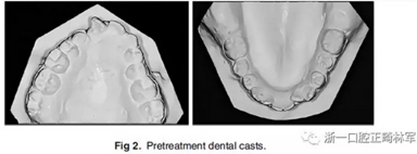

咬合關(guān)系:右側(cè)磨牙有II類關(guān)系傾向,尖牙關(guān)系II類;左側(cè)磨牙關(guān)系完全II類,尖牙關(guān)系I類。上頜雙側(cè)反合,中線稍有偏離。覆合、覆蓋減少。上頜中切牙向腭裂側(cè)旋轉(zhuǎn),上頜右側(cè)尖牙頰側(cè)異位萌出,雙側(cè)乳尖牙仍存在?;颊呱项M弓嚴重擁擠(擁擠度約10mm),下頜弓輕度擁擠4mm(擁擠度約4mm)(圖1 ;圖2)。牙周檢查良好。